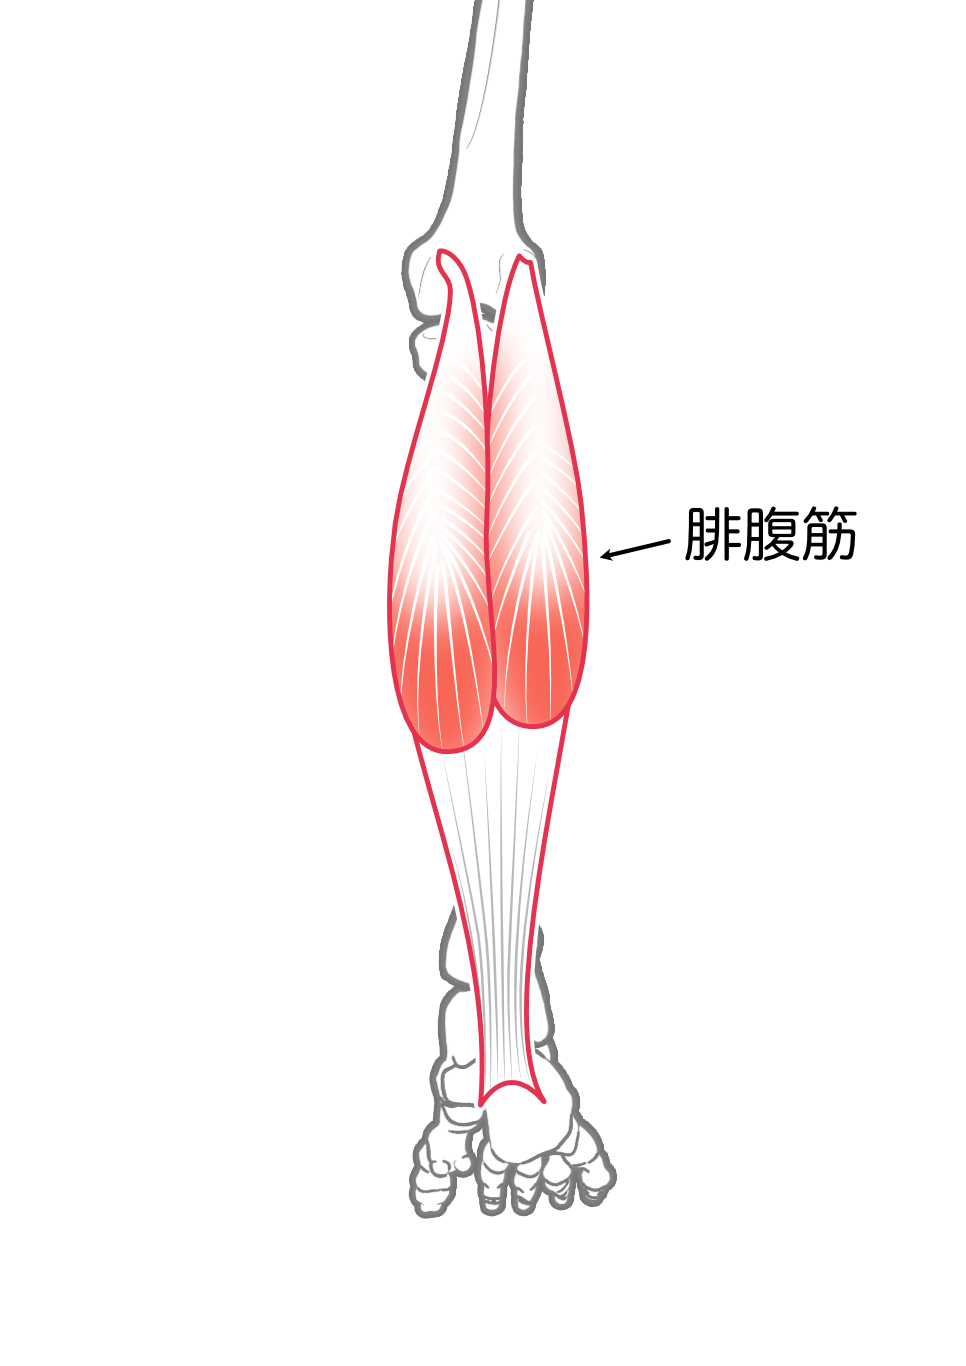

腓腹筋

| 起始 | 内側頭-大腿骨膝窩部, 大腿骨 内側上顆, 膝関節包 外側頭-大腿骨 外側上顆, 関節包 |

| 停止 | ヒラメ筋腱と合し, アキレス腱となり, 踵骨隆起につく |

| 神経 | 脛骨神経 L(4),5-S1,(2) |

| 作用 | 膝関節屈曲 |

- 腓腹筋